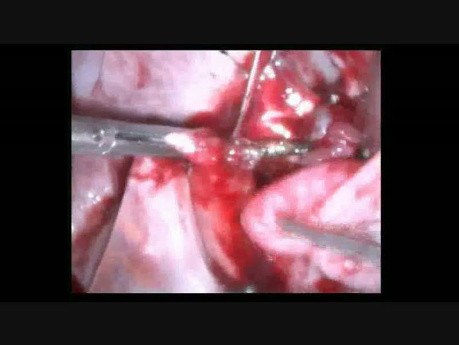

Résection de la corne utérine

C’est le cas vidéo d'une patiente enceinte PG, 10 + 3/7 SA, bHCG 15000 UI, RCF + et stable sans facteur de risque. Une grossesse interstitielle a été détectée à l'échographie endo-vaginale. Nous avons...

Grossesse extra-utérine intramurale à l'échographie...

C’est le cas vidéo d'une patiente enceinte en 10 + 3/7 SA, bHCG 15000 IU, Rythme Cardiaque Foetal + et stable sans facteur de risque. La grossesse interstitielle a été détectée par l'échographie transvaginale....